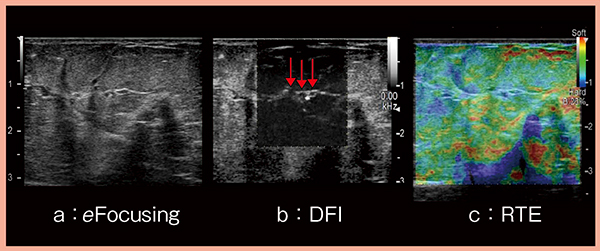

この病変は,マンモグラフィにて区域性石灰化と背景乳腺の濃度上昇域が認められる。DCIS成分は厚みがあるが,eFocusing(図4 a)で浅部から深部まで鮮明に描出されるため,病巣範囲の推測・同定が可能である。さらに,DFI(図4 b)にてDCIS周囲の低流速の血流を的確に描出しており,この穏やかな血流が病変を養っていると推測できる。RTE(図4 c)でも青く描出されており,FLRも5.77であった。

図4 症例3:3モードによるDCIS病巣の同定